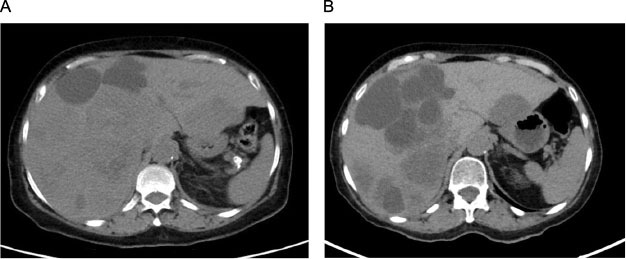

A 70-year-old woman presented with worsening right upper quadrant pain of 2 weeks duration, associated with anorexia and 10 lb weight loss. She had a history of right nephrectomy 13 months earlier for a grade 3, stage III pT3aNxM0 clear cell renal cell carcinoma (ccRCC), with extension to the renal vein and uninvolved margins; however, she did not follow up after surgery. No family history of cancer was reported. A computed tomography (CT) scan of her abdomen and pelvis disclosed hepatomegaly and several hypodense lesions throughout the liver parenchyma consistent with liver metastases (Figure 1A). Labs were remarkable for a hemoglobin level of 11.2 g/dL and an elevated serum lactate dehydrogenase level of 612 U/L.

Figure 1: (A) Computed tomography (CT) abdomen and pelvis (pre-treatment) showing hepatomegaly and several hypodense lesions throughout the liver parenchyma consistent with liver metastases. (B) CT abdomen and pelvis (post-treatment) showing enlargement of existing lesions and new hepatic metastases.

The patient was started on pembrolizumab 200 mg intravenously every 3 weeks and axitinib 5 mg orally twice daily as first-line therapy for her recurrent/metastatic disease after completing full restaging, which was otherwise negative. She required dose reduction of her axitinib to 3 mg twice daily due to fatigue, and experienced elevated thyroid stimulating hormone (TSH) of 16.5 mcIU/mL (normal free T4), which improved on levothyroxine. Unfortunately, after completing 12 weeks on combination axitinib/pembrolizumab, repeat CT scans for assessment of response disclosed progression of liver metastases (Figure 1B).